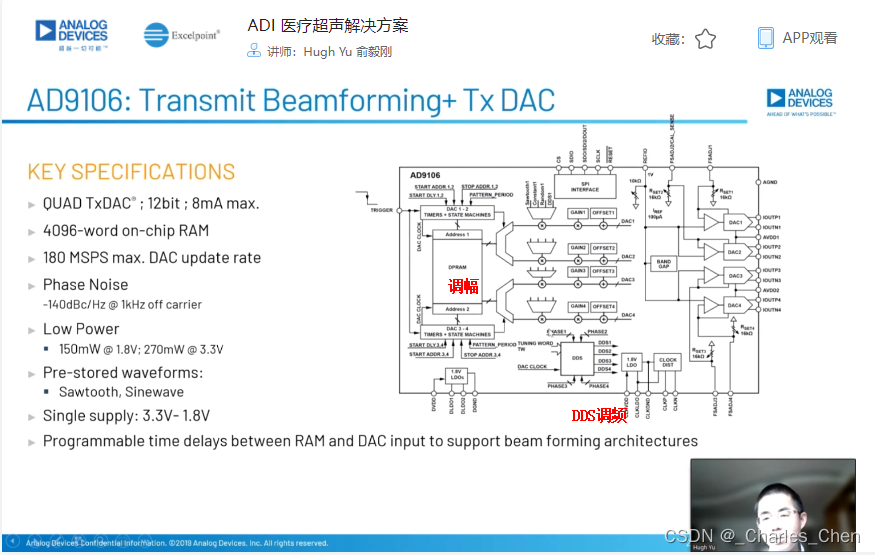

数字发射波束成形器用于产生所要求的数字发射信号,以正确的时间和相位生成聚焦发射信号。高性能超声系统可通过任意波形发生器产生复杂的发射波形,从而优化图像质量。这些情况下,发射波束成形器以大约40MHz速率生成8位至10位数字字符,并以此产生所要求的发射波形。数/模转换器(DAC)将数字波形转换成模拟信号,通过线性高压放大器进行放大,用于驱动传感器单元。由于这种发射技术占用较大体积,而且价格昂贵、需要消耗较高能量,所以,这种架构只限于昂贵的非便携设备。多数超声系统并不使用这种发射波束成形技术,而是采用多级高压脉冲发生器产生需要发射的信号。在这种替代方案中,利用高集成度、高压脉冲发生器快速切换传感器单元至适当的可编程高压电源,产生发射波形。为了产生一个简单的两极发射波形,脉冲发生器需要交替地将传感器单元切换到由数字波束成形器控制的正、负发射电压。更复杂的设计可以让传感器单元切换至多路电源和地,从而产生更复杂、性能更好的多重波形。